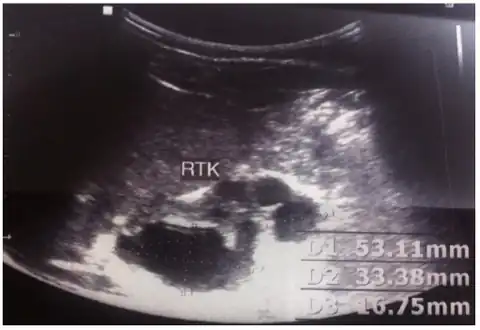

Diagnostic methodUltrasound[1]

The cause includes a numbers of genetic mutations and exposure to certain drugs or medications during pregnancy.[1] The underlying mechanism involves urine being unable to flow through the tubules within the kidneys resulting in cyst formation.[1] Diagnosis is generally by ultrasound, either before or after birth.[1]

MCDK is usually diagnosed by ultrasound examination before birth. Mean age at the time of antenatal diagnosis is about 28 weeks[10] A microscopic analysis of urine in individuals with probable multicystic dysplastic kidney should be done.[8]One meta-analysis demonstrated that unilateral MCDK occurs more frequently in males and the greater percentage of MCKD occur on the left side of the body.[11]